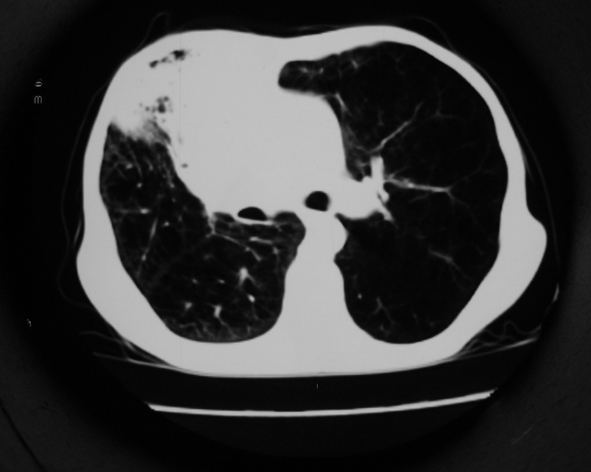

男53岁,咳嗽气短,以往身体健康.

右肺上叶多发多形态空洞及增殖灶,可见团块钙化,胸膜肥厚、粘连,考虑继发型肺结核可能性大

1.右肺上叶干酪性肺炎,2。肺气肿,肺大泡

支持右上肺继发性肺结核并干酪性肺炎,右肺大泡,左肺代偿性气肿。